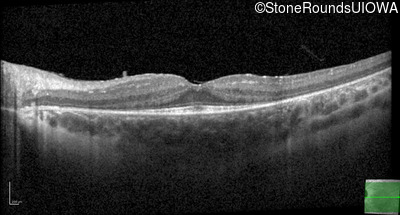

Age at visit: 8 years